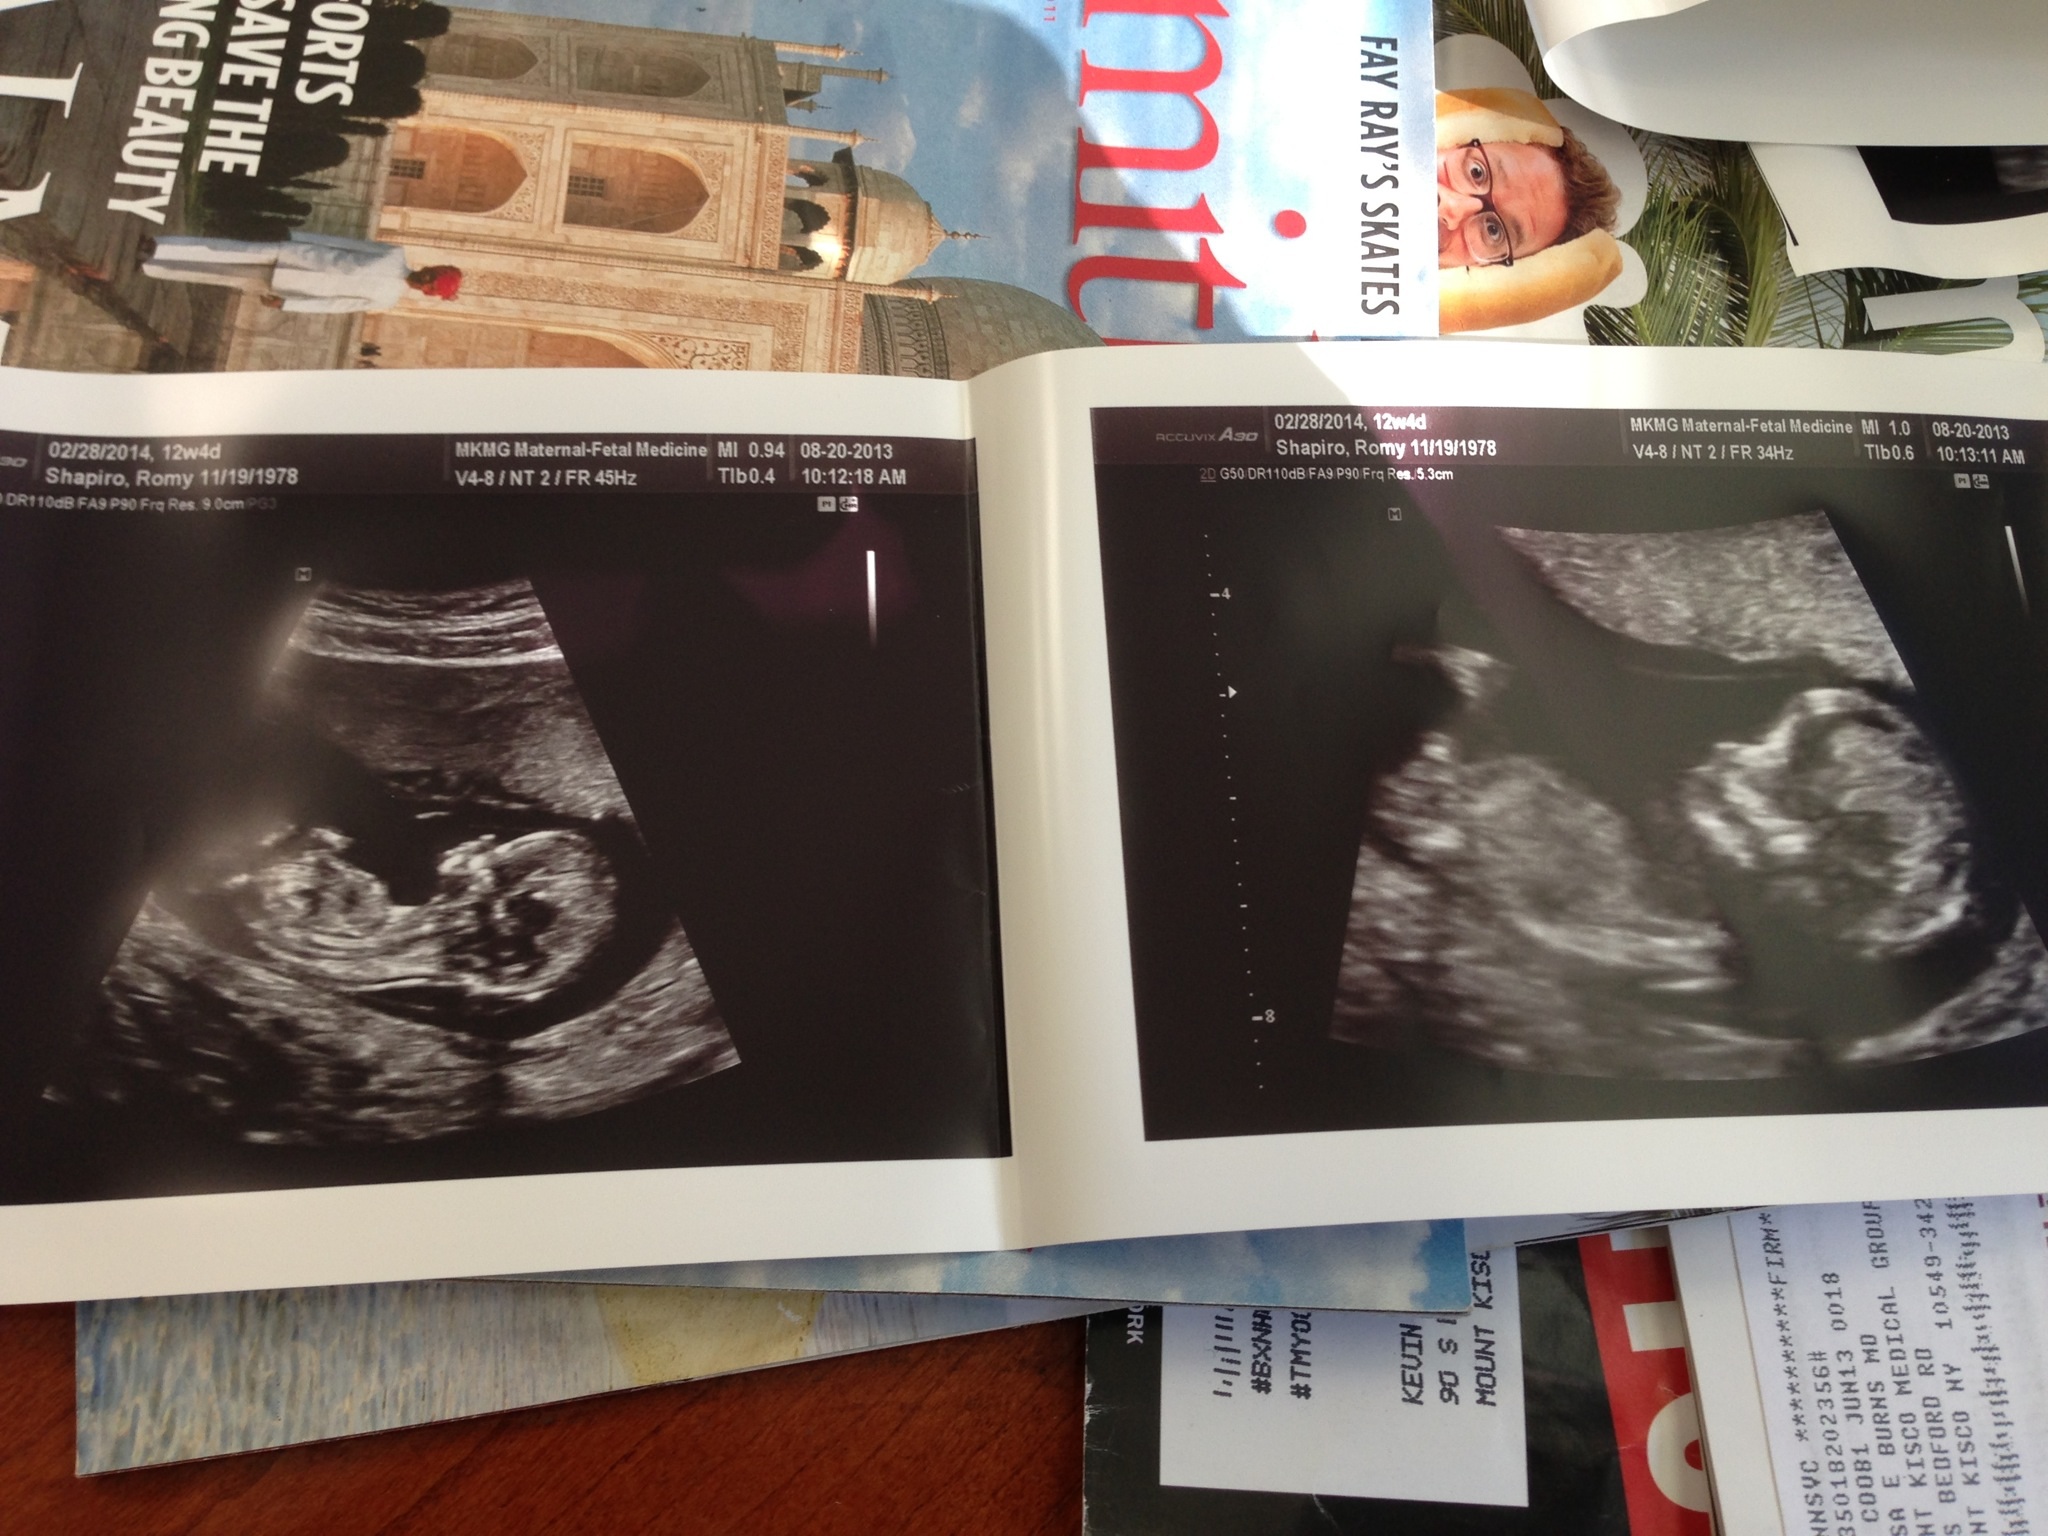

help!!! Tech says this is cord or leg and not nub. Is she telling the truth?!?!